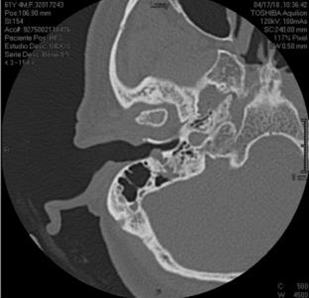

A 61-year-old woman was evaluated by otology for right peripheral facial paralysis with a six months evolution period, initially managed with steroids and Acyclovir without therapeutic response. Physical examination revealed facial motility House-Brackman VI/VI of the right side and I/VI of the left side, an erythematous lesion covered by skin in the right posterior inferior region of the external auditory canal (EAC), and bright tympanic membrane without fluid in the middle ear. In addition, the hearing tests showed a positive bilateral Rinne, and a Weber centered with tuning forks of 512 -256 Hz. Moreover, a simple CT scan of the ear showed attenuation and bony erosion of the stylomastoid foramen, mastoid portion of the facial nerve, and right EAC (Figure 1 & 2).

Figure 1 CT of an axial slice of a single ear in the bony canal. Lesion involving the right stylomastoid foramen, the mastoid portion of the facial nerve, and EAC, eroding its posterior wall.